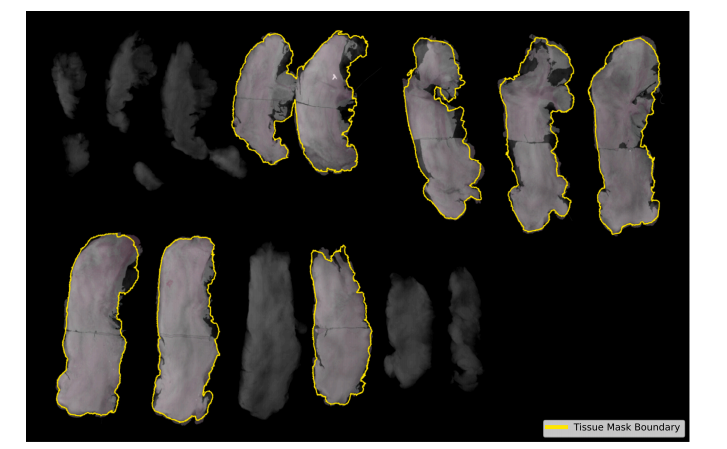

Fig. 4. Visual assessment of the PViT-AIR registered histopathology and faxitron images for a typical case (average landmark error: 1.12 mm, average stitching distance: 0.69 mm).PViT-AIR generates robust alignments and closes the gap between histopathology images in all macrosections available for this study

图4. 对PViT-AIR配准的组织病理图像和传真X射线图像进行的视觉评估,展示了一个典型案例(平均标志点误差:1.12毫米,平均拼接距离:0.69毫米)。PViT-AIR生成了稳健的对齐,并成功消除了所有本研究中可用宏观切片之间的组织病理图像的间隙。